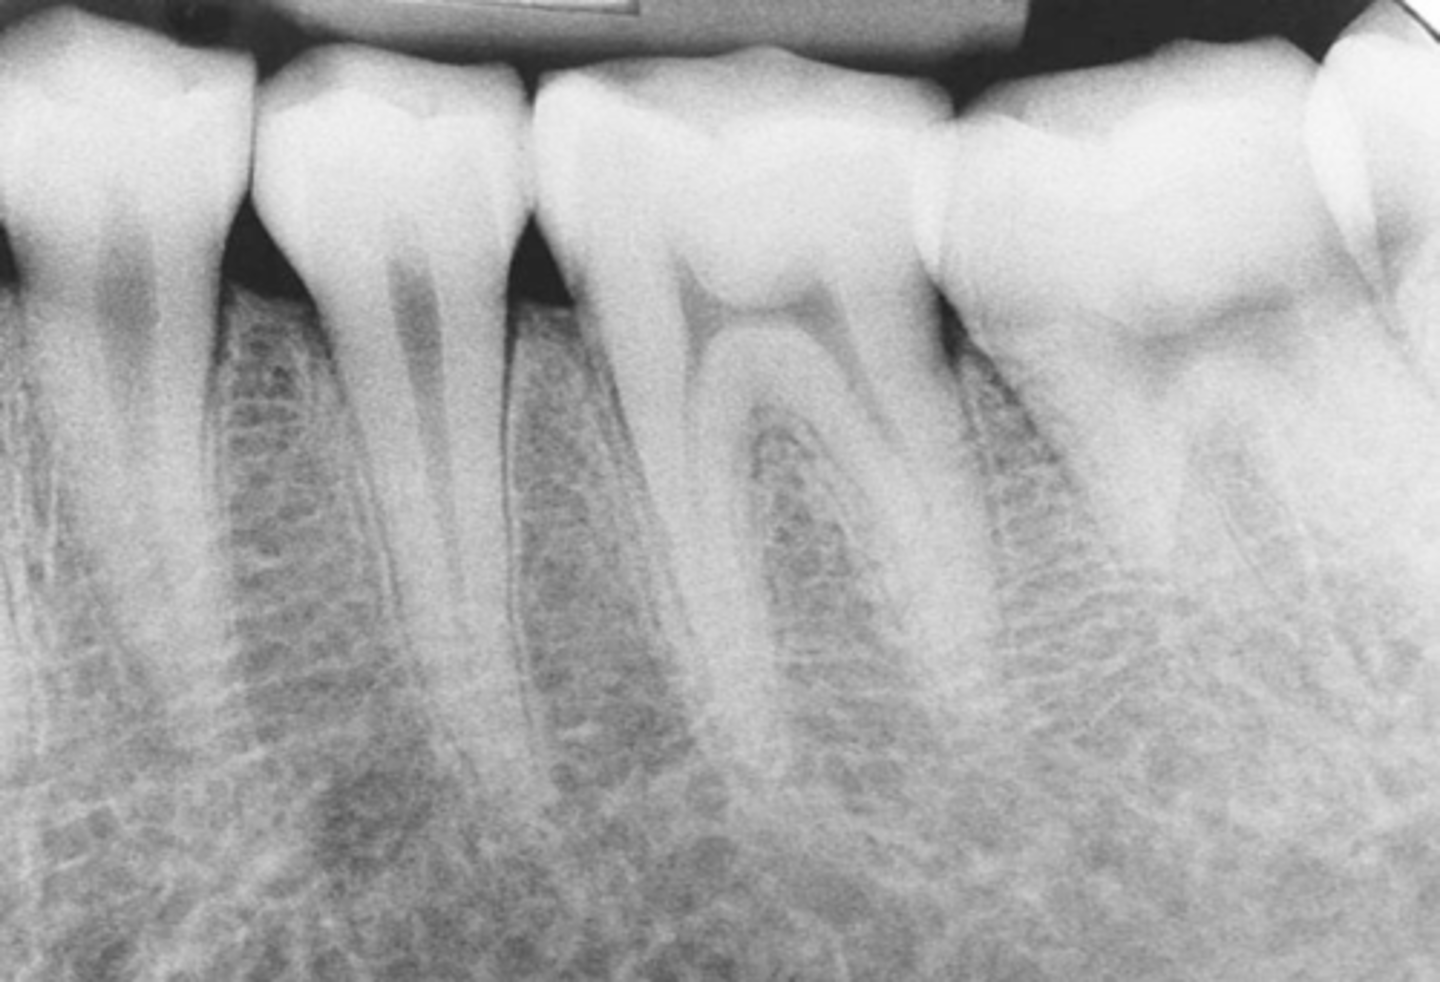

Example of a periapical x-ray:

How many teeth does periapical imaging usually display?

- two to four teeth.

What anatomy is demonstrated in periapical imaging? What kind of information?

• Provides detailed information about the teeth and the surrounding alveolar bone

• Demonstrates crown to apex.

• At least 2mm bone, ideally 5mm beyond apex.